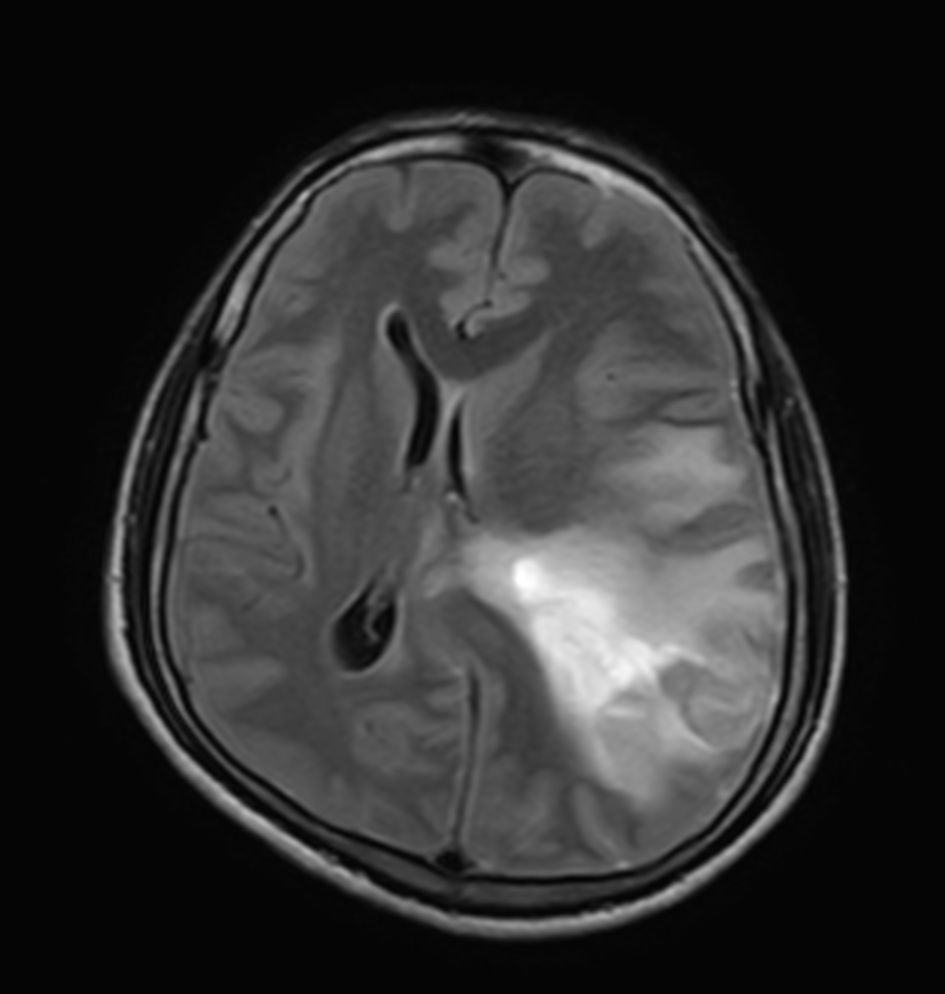

Pediatric Brain with hemorrhagic mass

Pediatric patient with a hemorrhagic mass in the brain